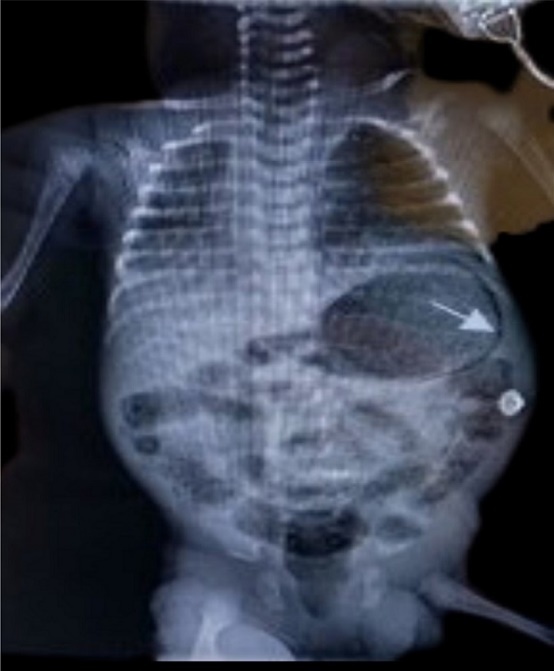

A late preterm (gestational age 35+2/40) male neonate was born to a 25-year-old multiparous woman with minimal antenatal care (5 visits). Her booking parameters were unremarkable and her antenatal period reportedly uneventful. She presented with preterm, prolonged, pre-labour rupture of membranes (PPPROM) and was therefore induced with Cytotec® (Misoprostol); liquor was said to be clear. There were no signs of chorioamnionitis and no antibiotics or steroids were given during delivery. He was delivered via spontaneous vaginal delivery (SVD), and was suctioned; nil other active resuscitation was required. APGARs were 9 and 9 at 1 and 5 minutes respectively. Essential newborn care was offered. Initial examination was unremarkable with temperature of 36.8C. He was of low birth weight at 2.46 kg. He was allowed to room in with his mother on the postnatal ward; however by 6 hours of life he was notably distressed characterized by grunting and accessory muscle use, despite a normal respiratory rate of 56. Pre and post ductal saturations were acceptable (97% respectively).Given the presence of danger signs and his history of prematurity on a background of PPPROM, he was admitted to the Neonatal Intensive Care Unit (NICU), nursed in an isolette, attached to cardiac monitor and was screened. Blood and urine culture were taken, complete blood count documented and Chest X-ray (C-XRAY) requested. He was started on ampicillin and gentamycin which are first line antibiotics based on our local protocol. He required mixed gases via nasal cannula on admission and oxygen saturations were maintained between 88 – 92%. A cow’s milk protein base formula was offered due to the unavailability of breastmilk. He was fed via the orogastric tube (OGT) due to respiratory distress, however due to minimal coffee ground secretions subsequently being noted via OGT, he was kept nil per oral (NPO). C-XRAY findings were in keeping with Congenital Pneumonia, and abdominal XRAY (A- XRAY) was unremarkable. The coffee ground secretions resolved spontaneously, and was attributed to mucosal irritation by the feeding tube. Arterial blood gas done showed compensated metabolic acidosis and hyperoxia. Blood and urine cultures were sterile. By day 3 of admission he was no longer distressed, and respiratory support was discontinued. He was able to resume feeds after being NPO for 48 hours. By day 7 of life however, where discharge was imminent he was noted to be irritable and lethargic, with subsequent abdominal distension. He then had regurgitation episodes and appeared very ill looking. Abdominal examination was significant for mild distension, however his abdomen remained non-tender, with no skin changes or visible bowel loops. Ileus secondary to sepsis was entertained. A-XRAY revealed linear serpiginous radiolucency circumferentially around gastric bubble and within bowel wall primarily within the right lower quadrant see Figure 1.

Figure 1.Anterior posterior abdominal radiograph showing gastric pneumatosis (arrow shown) and pneumatosis intestinalis.

Anterior posterior abdominal radiograph showing gastric pneumatosis (arrow shown) and pneumatosis intestinalis.